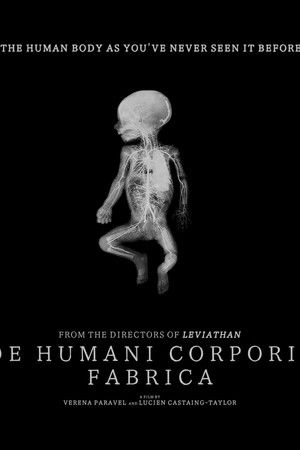

De humani corporis fabrica

(2023)Overview

An extraordinary adventure through the interior of the human body; or the discovery of an alien landscape of unprecedented beauty.

- Documentary